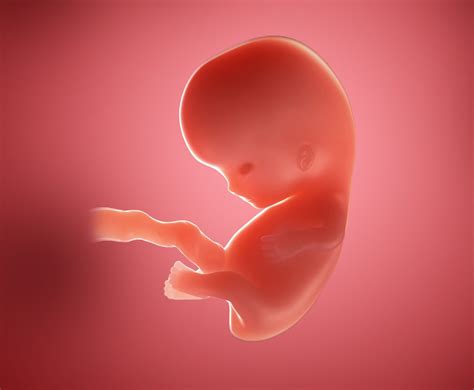

8 Week Baby

• baby at 8 weeks gestation

• 8 weeks pregnant baby development

• baby 8 weeks pregnant pictures